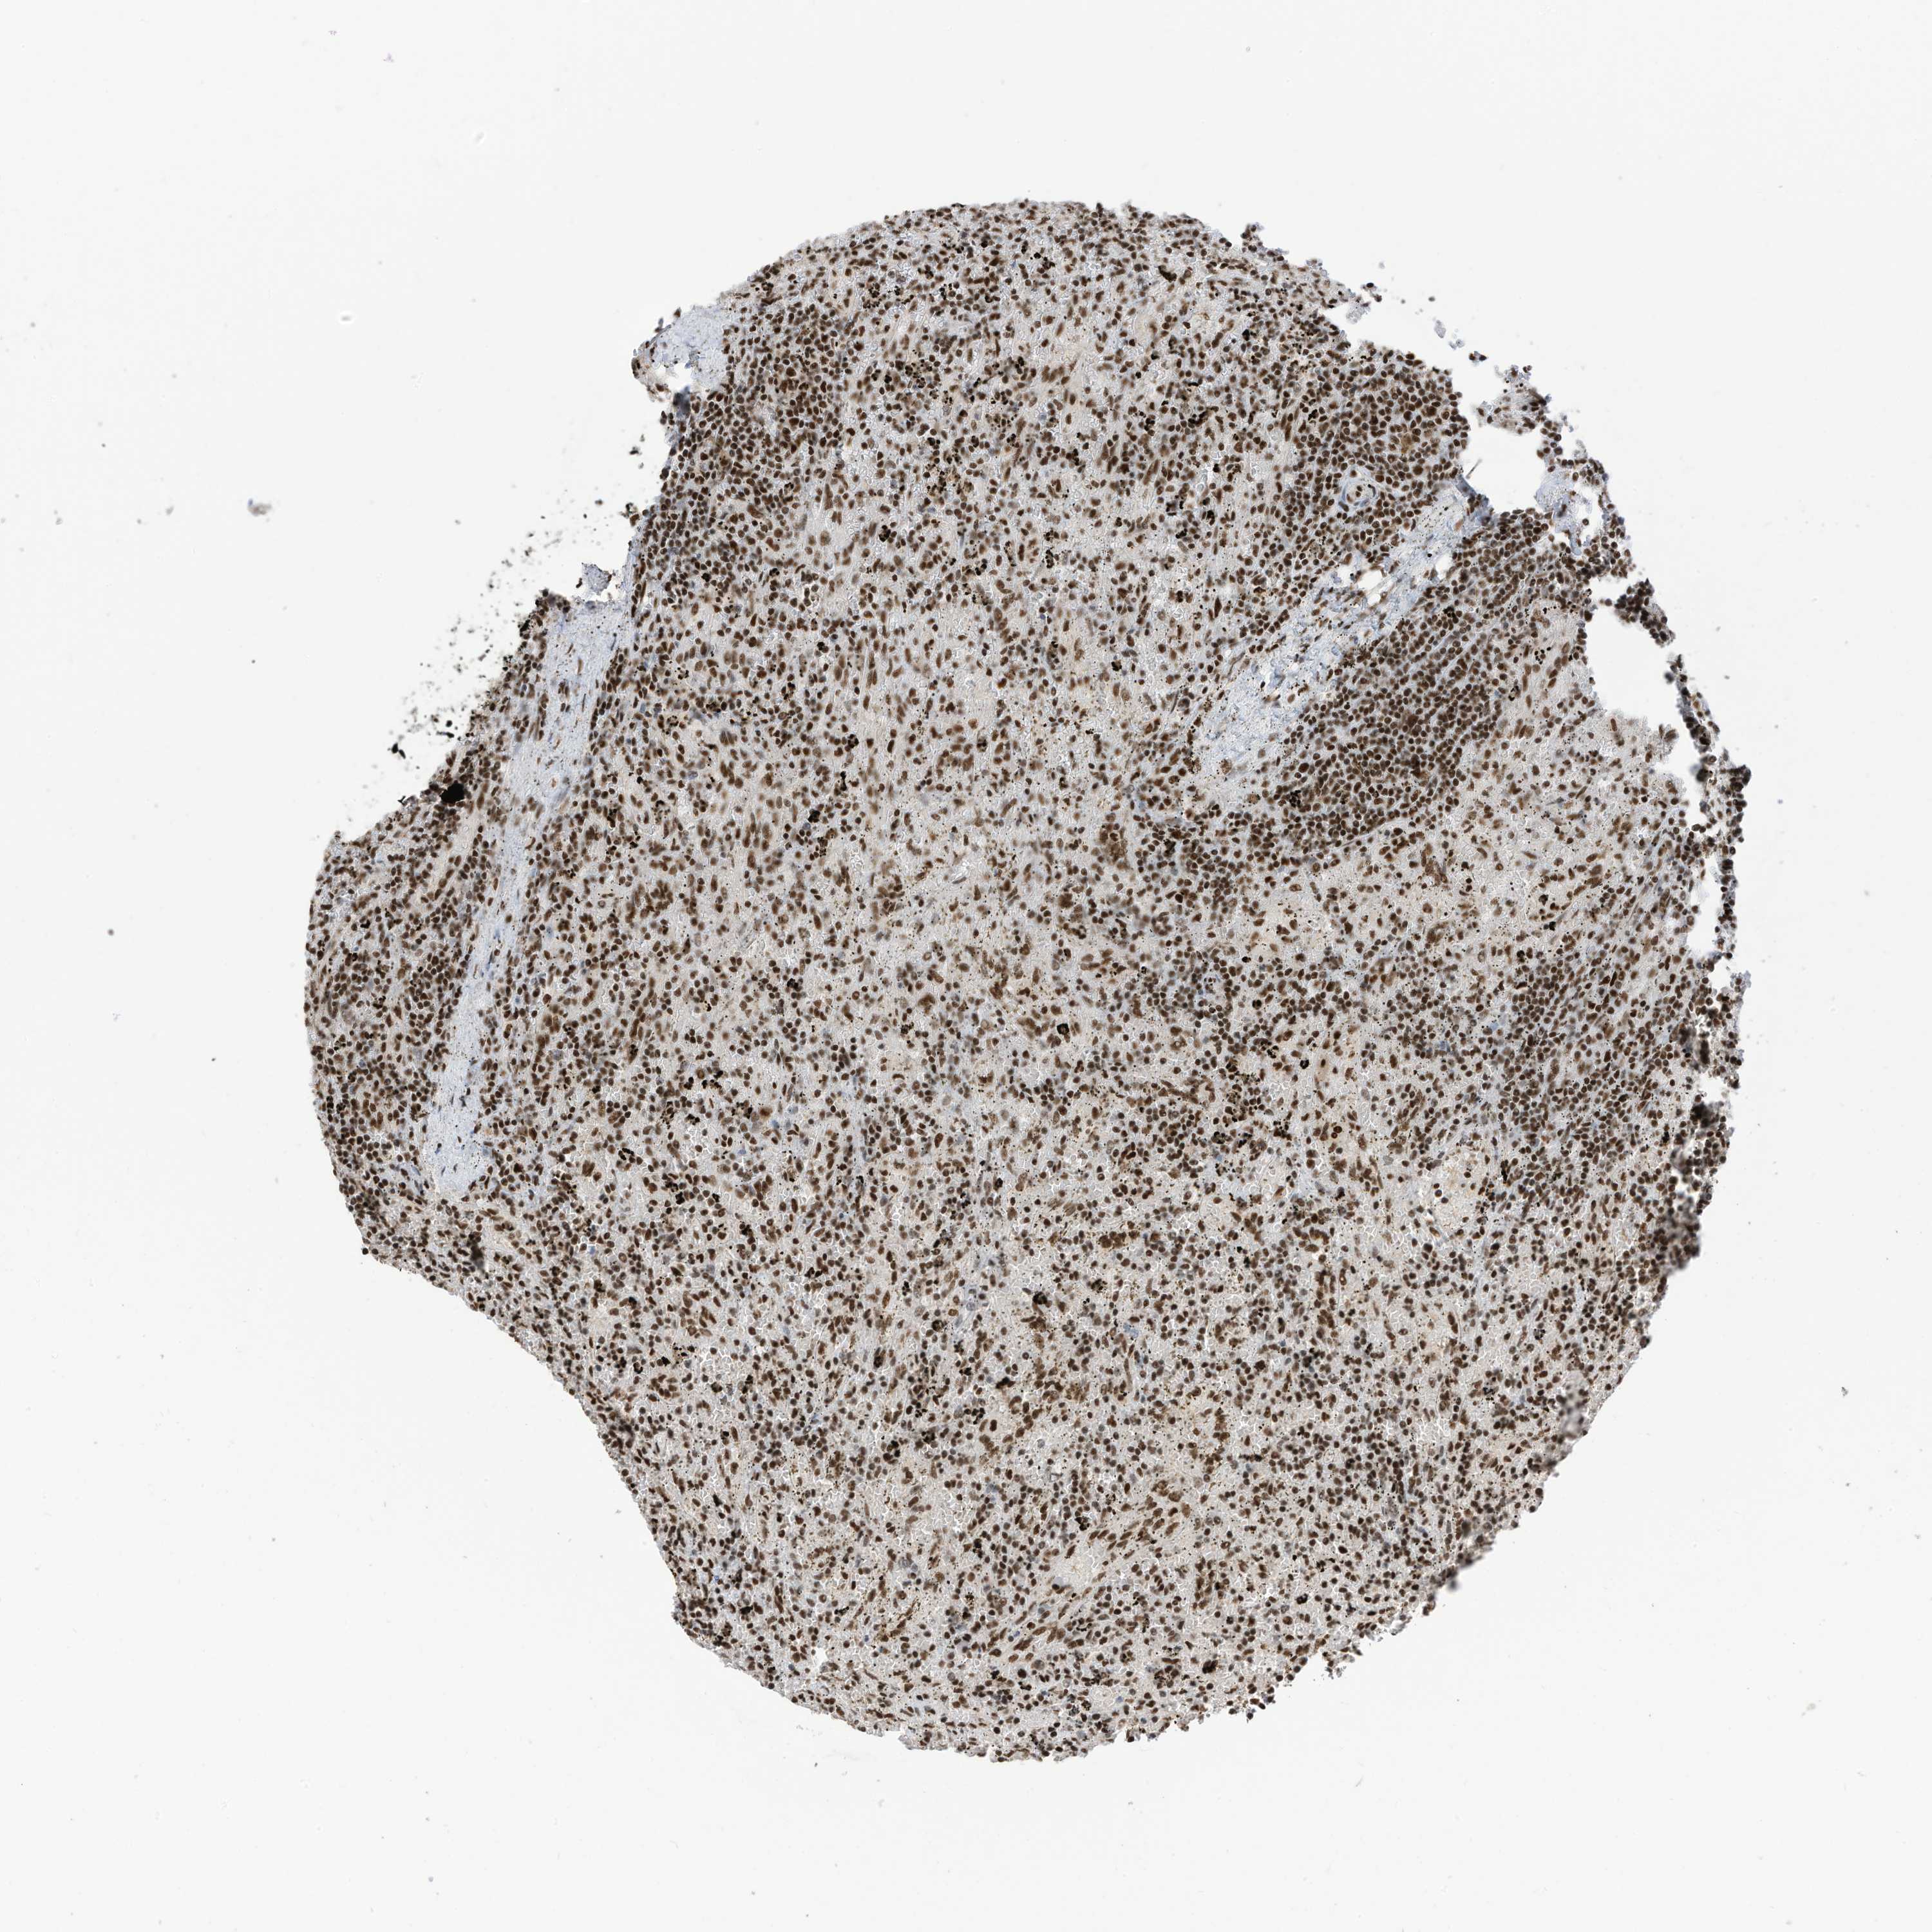

LYMPHOMA - Protein expressioni

A mouse-over function shows sample information and annotation data. Click on an image to view it in a full screen mode. Samples can be filtered based on level of antibody staining by selecting one or several of the following categories: high, medium, low and not detected. The assay and annotation is described here.

Antibody stainingi

Antibody staining in the annotated cell types in the current human tissue is reported as not detected, low, medium, or high, based on conventional immunohistochemistry profiling in selected tissues. This score is based on the combination of the staining intensity and fraction of stained cells.

Each image is clickable and will lead to virtual microscopy that enables deeper exploration of all samples and also displays staining intensity scores, fraction scores and subcellular localization as well as patient and tissue information for each sample.

Antibody HPA032055

Staining

High

Intensity

Strong

Quantity

>75%

Location

Nuclear

Hodgkin's disease, NOS

Malignant lymphoma, non-Hodgkin's type, High grade

Malignant lymphoma, non-Hodgkin's type, Low grade